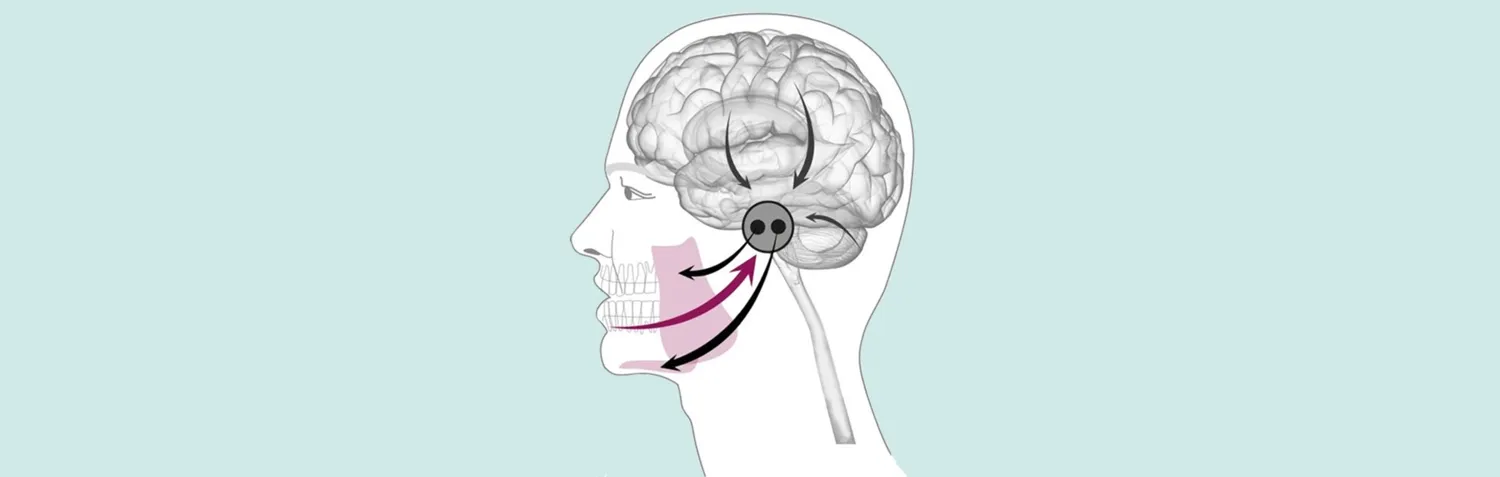

Vårt arbete sträcker sig från att kartlägga de biologiska mekanismerna bakom kronisk orofacial smärta, med hjälp av biomarkörer, muskelmikrobiopsier och longitudinella epidemiologiska samt kliniska studier, till att öka förståelsen för hur bitning, tuggning och oral sensorimotorisk kontroll utvecklas från barndom till äldre åldrar.

Vi har varit pionjärer i att utveckla nya metoder för att studera käkens motoriska fysiologi, sensorisk-motorisk integration och tuggmönster, inklusive utvecklingen av viskoelastiska testfödor och träningsparadigm som syftar till att förbättra oral funktion och främja ett hälsosamt åldrande. Vår forskning undersöker också hur nedsatt tuggförmåga bidrar till undernäring och kognitiv försämring hos äldre, samt om störningar i rytmen för tuggning och sväljning kan kopplas till tillstånd som anorexi, bulimi eller fetma. Vidare har vår forskargrupp utvecklat en mikrodialysteknik samt en mikrobiopsiteknik som tillåter både mikrodialys och mikrobiopsitagning från ansiktet för att kunna undersöka mekanismer bakom orofacial smärta men också hur behandlingar påverkar musklerna.